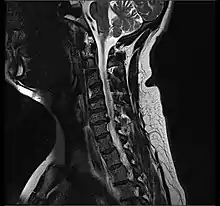

Cervical disc herniation

Herniated disc at C6–C7 level

Cervical disc herniations occur in the neck, most often between the fifth and sixth (C5–6) and the sixth and seventh (C6–7) cervical vertebral bodies. There is an increased susceptibility amongst older (60+) patients to herniations higher in the neck, especially at C3–4.[22] Symptoms of cervical herniations may be felt in the back of the skull, the neck, shoulder girdle, scapula, arm, and hand.[23] The nerves of the cervical plexus and brachial plexus can be affected.[24]

• Magnetic resonance imaging is the gold standard study for confirming a suspected LDH. With a diagnostic accuracy of 97%, it is the most sensitive study to visualize a herniated disc due to its significant ability in soft tissue visualization. MRI also has higher inter-observer reliability than other imaging modalities. It suggests disc herniation when it shows an increased T2-weighted signal at the posterior 10% of the disc. Degenerative disc diseases have shown a correlation with Modic type 1 changes. When evaluating for postoperative lumbar radiculopathies, the recommendation is that the MRI is performed with contrast unless otherwise contraindicated. MRI is more effective than CT in distinguishing inflammatory, malignant, or inflammatory etiologies of LDH. It is indicated relatively early in the course of evaluation (<8 weeks) when the patient presents with relative indications like significant pain, neurological motor deficits, and cauda equina syndrome. Diffusion tensor imaging is a type of MRI sequence used for detecting microstructural changes in the nerve root. It may be beneficial in understanding the changes that occur after herniated lumbar disc compresses a nerve root, and might help in differentiating the patients that need surgical intervention. In patients with a high suspicion of radiculopathy due to lumbar disc herniation, yet the MRI is equivocal or negative, nerve conduction studies are indicated.[43] T2-weighted images allow for clear visualization of protruded disc material in the spinal canal.